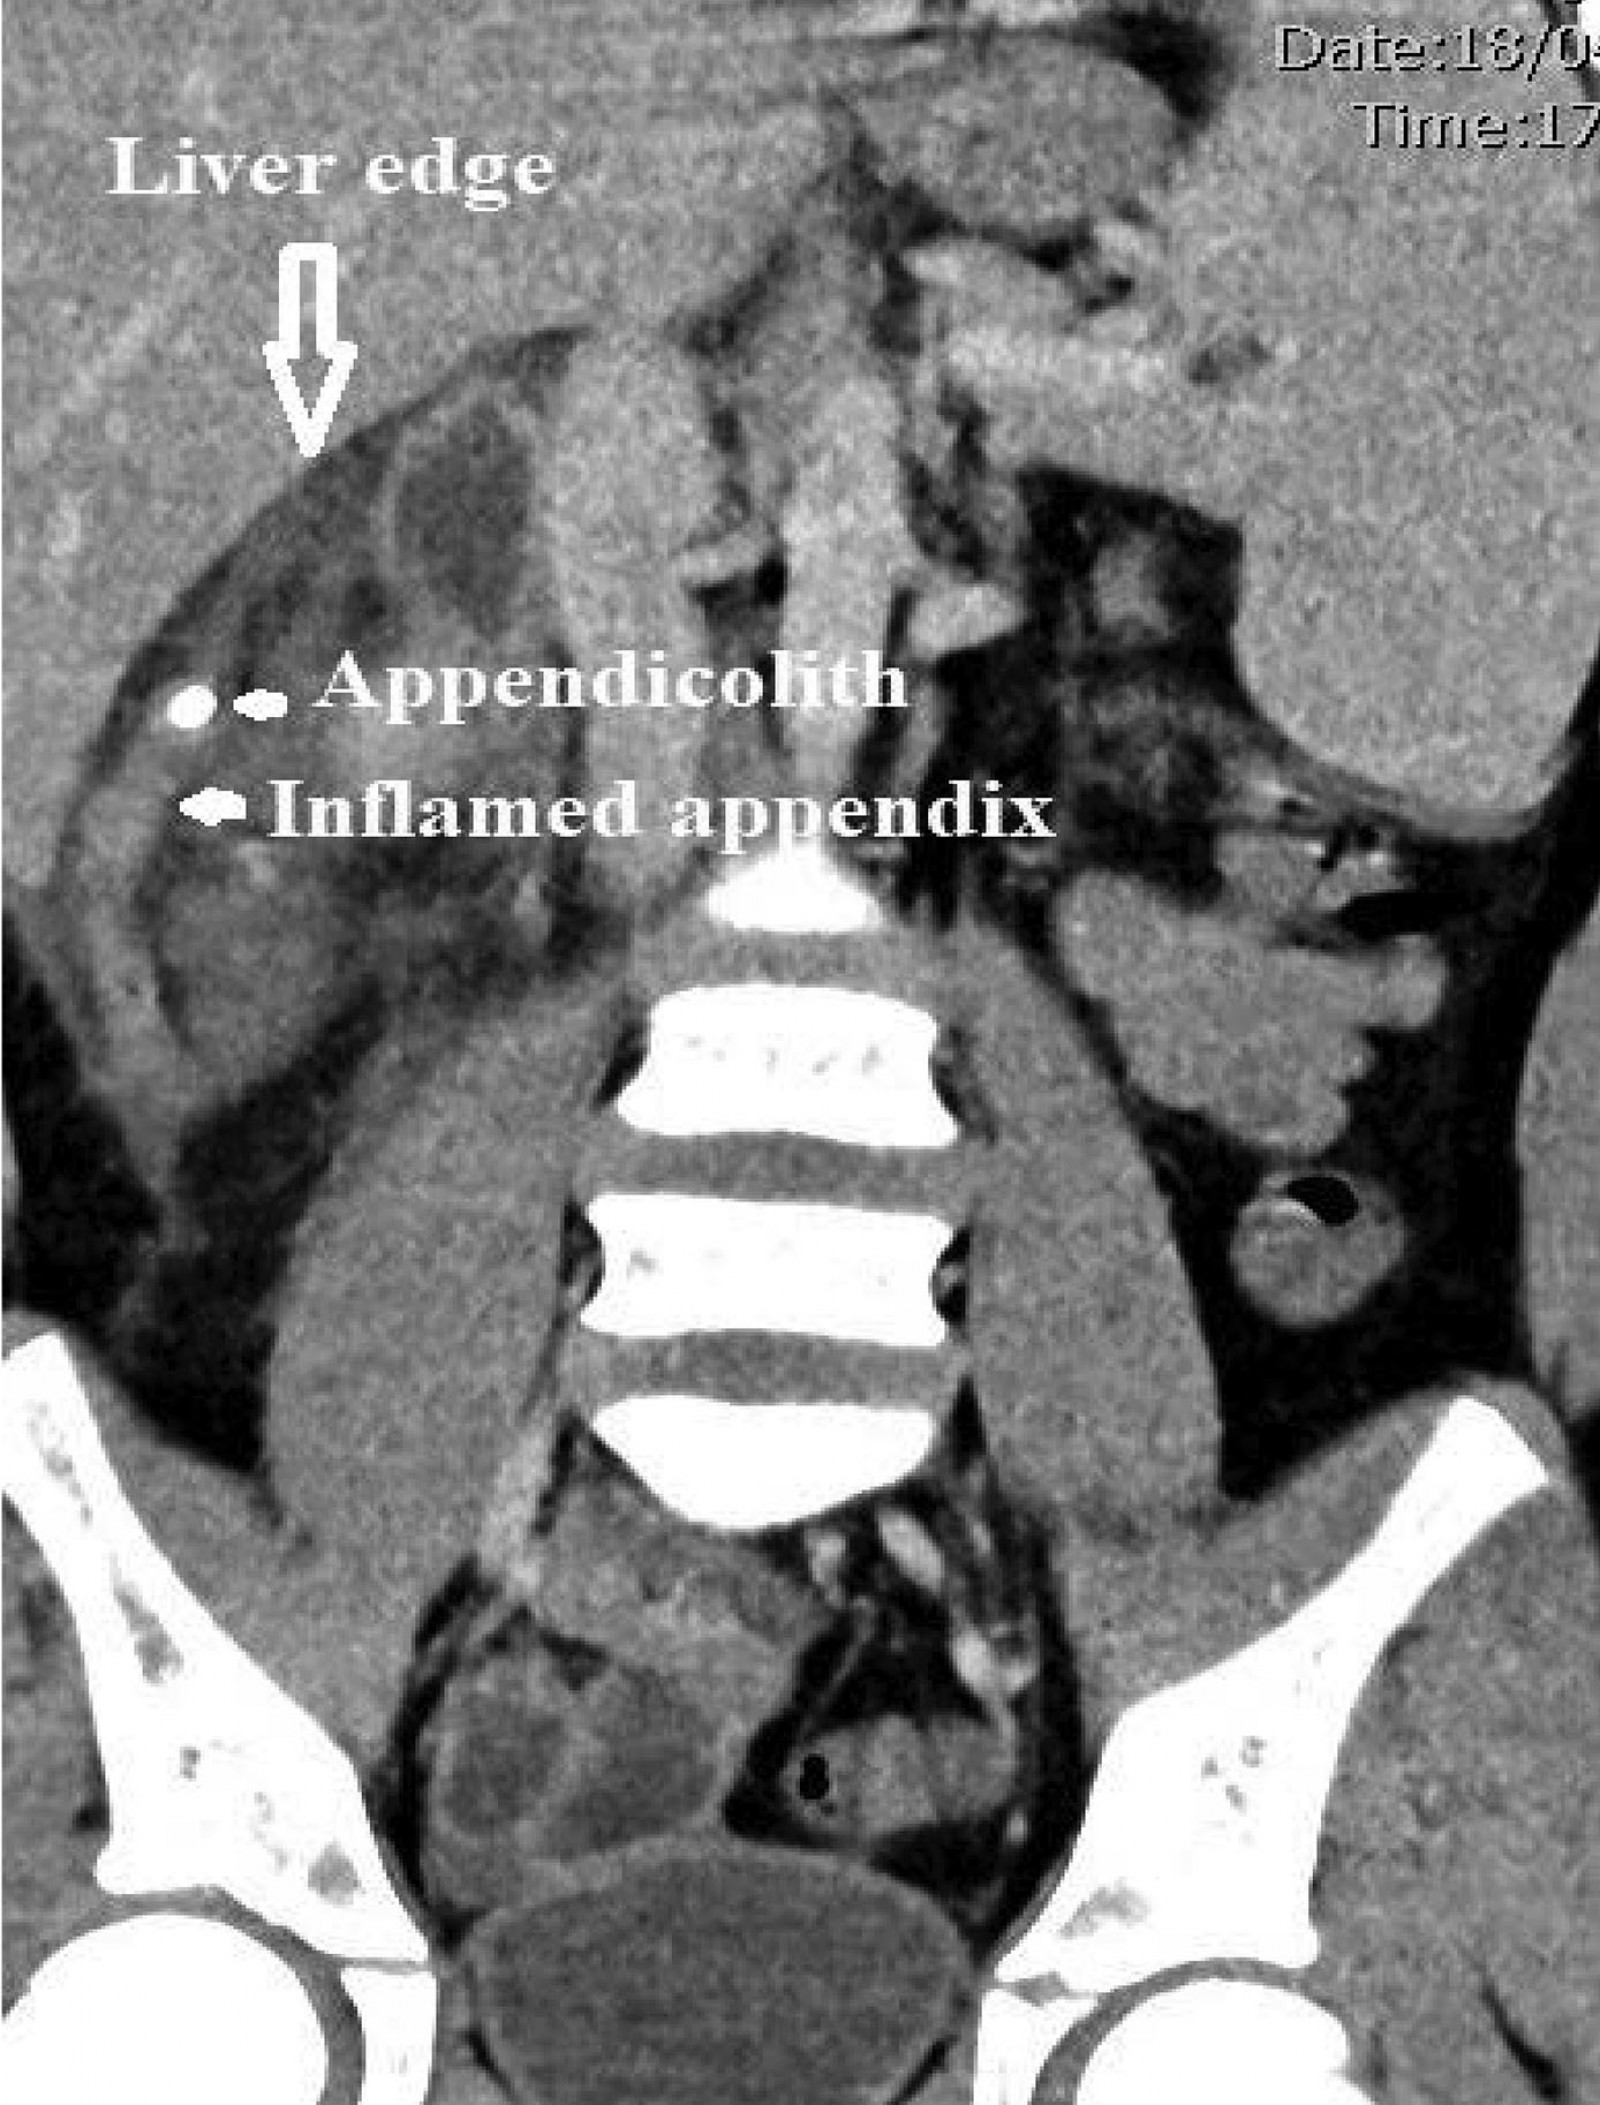

Considering the severity of symptoms and the presence of possible peritonitis, a CT scan of the abdomen and pelvis was performed. The scan showed a markedly thickened, hypoechoic tubular structure medial to the inferior edge of the liver, located retrocaecally (Fig1). The adjacent small bowel loops, hepatic flexure and caecum were thickened (Fig2). The CT scan also demonstrated localised extraluminal gas in the subhepatic region, consistent with perforation. An emergency laparotomy revealed a perforated, gangrenous appendix. The patient’s recovery period was uneventful, and he was discharged on the fourth day after surgery.

Figure 1: CT scan showing inflamed appendix in subhepatic location with an appendicolith close to the tip.